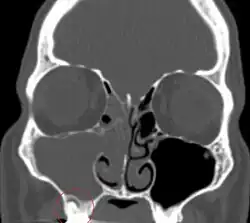

Odontogenic sinusitis

Sinusitis is inflammation of the paranasal air sinuses. Odontogenic sinusitis is an inflammatory condition of the paranasal sinuses that is the result of dental pathology, most often resulting from prior dentoalveolar procedures, infections of maxillary dentition, or maxillary dental trauma.[6] Infections associated with teeth may be responsible for approximately 20% of cases of maxillary sinusitis.[7] The cause of this situation is usually a periapical or periodontal infection of a maxillary posterior tooth, where the inflammatory exudate has eroded through the bone superiorly to drain into the maxillary sinus. Medical management and treatment of the underlying dental pathology remains a critical initial step in the treatment of odontogenic sinusitis, however recent literature suggests that a significant portion of patients may require endoscopic sinus surgery for successful disease resolution.[6] Once an odontogenic infection involves the maxillary sinus, it is possible that it may then spread to the orbit or to the ethmoid sinus.[7]